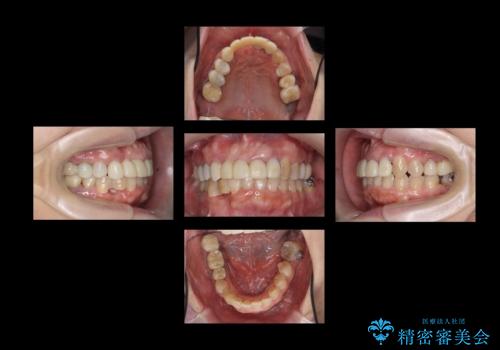

- 50代女性

- 2年

- 10-30回

- 全体的な虫歯治療、根管治療、および歯周病治療を行いました。

歯周病治療につきましては歯周ポケット除去のために歯周外科処置(APF)を行っています。

左下6の欠損については左下7はワイヤー部分矯正でアップライトを行い、補綴スペースを確保しています。

右下犬歯は歯周病の進行が重度のため、やむなく抜歯をし、骨増生後にインプラント埋入を行っています。